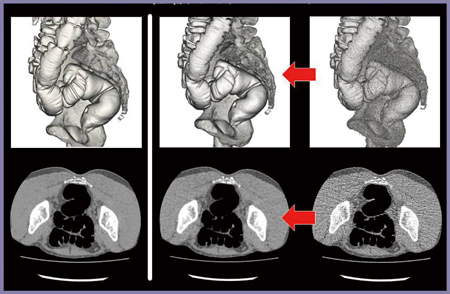

■症例2:HP111と0.35s/rotの併用(図2)

HP111と0.35s/rotを併用した高速撮影の例を示す。症例2では,仰臥位で病変が残液内に埋もれているが,水溶性造影剤でタギングされているため,病変の指摘が可能である。通常の撮影条件では,撮影に7.4秒を要するが,高速スキャンを用いることで約3秒での撮影が可能で,内腔像で残液に埋もれた病変を明瞭に描出できた。コロナル画像も遜色のない画像を得られた。

図2 症例2:HP111と0.35s/rotの併用

撮影時間は約3秒